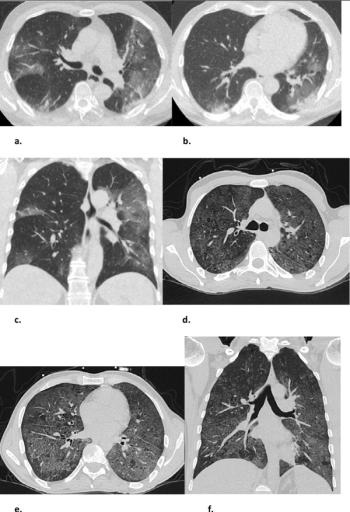

For patients who have had viral symptoms for more than 48 hours, combining chest CT findings and CO-RADS classifications can effectively diagnose COVID-19-positive patients.